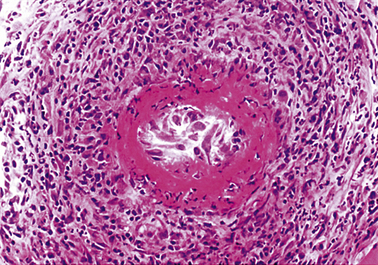

The characteristic histological lesion of malignant hypertension is fibrinoid necrosis of small arteries and arterioles (Fig. 13.12). The kidney is frequently affected and some degree of renal dysfunction is inevitable. Occasionally there is massive proteinuria, and renal failure develops. Acute left ventricular failure can occur.

image

Fig. 13.12 Malignant hypertension. There is fibrinoid necrosis (red) in the wall of a medium-sized renal artery. Glomeruli are below and to the right of this artery.